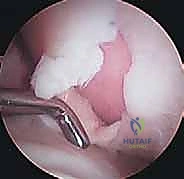

Step 6: Graft Delivery and Impaction

- Graft Placement:

- Surgical Directive: "Retrieve the first harvested plug from the holding solution. I'll need the graft inserter from the COR system."

- Technique:

- "Carefully load the